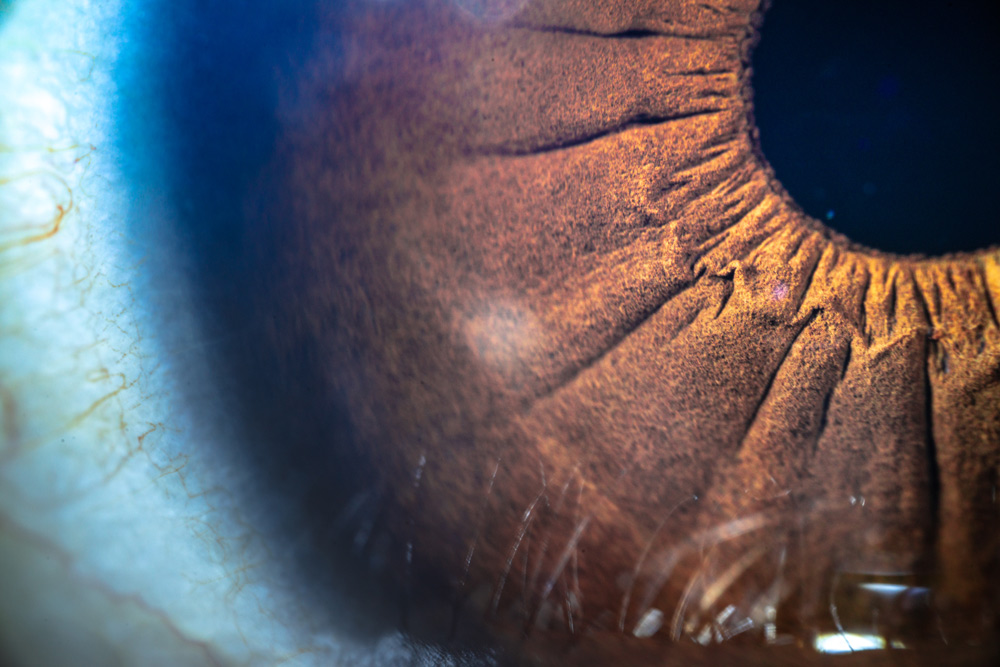

Cornea

With the need for quality donor corneal tissue outstripping supply, especially outside the U.S., there is an interest in expanding the donor pool. While the EBBA doesnโt explicitly exclude donors with diabetes,1 this disease status has called into question the quality of the tissue and endothelial health for more advanced procedures like DMEK.